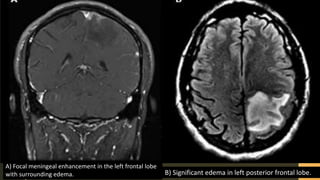

B) Significant edema in left posterior frontal lobe.

A) Focal meningeal enhancement in the left frontal lobe

with surrounding edema.

z B) Significant edemain left posterior frontal lobe. A) Focal meningeal enhancement in the left frontal lobe with surrounding edema.